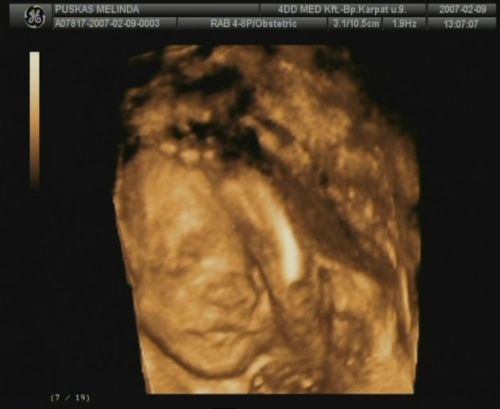

Ja lányok, csak, hogy untassalak titeket, tegnap az egyik barátom megmutatta, hogy kell dvd felvételről kimenteni képeket, így Domcsiról lementettem pár tuti képet! Mellékelem, remélem nem baj:

Kép Kép Kép Kép Kép

Untatni? édes képekkel lehet szerinted minket untatni? Ezek nagyon cukik! Édes nagyon a babád!

Az ásítós, meg az első, a szemvakargatós, az igen :)

olyan mintha azt akarná mondani, hogy minek keltettetek fel, hát hagyjatok már békén, itt már aludni se lehet?

Hát nagyon cuki, az ilyen képekkel nem lehet betelni :)